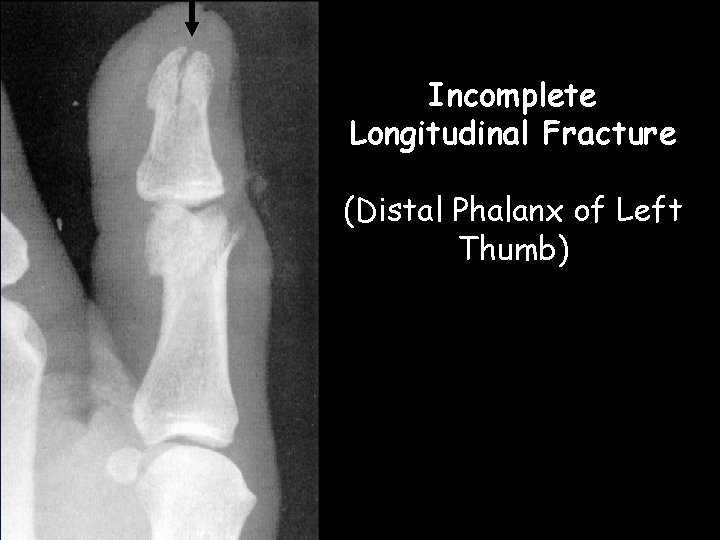

Incomplete Longitudinal Fracture (Distal Phalanx of Left Thumb)